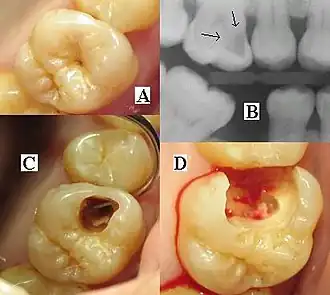

| Destruction of a tooth by dental caries and disease | |

Tooth decay, also known as caries,[a] is the breakdown of teeth due to acids produced by bacteria.[6] The resulting cavities may be many different colors, from yellow to black.[1] Symptoms may include pain and difficulty eating.[1][2] Complications may include inflammation of the tissue around the tooth, tooth loss and infection or abscess formation.[1][3] Tooth regeneration is an ongoing stem cell–based field of study that aims to find methods to reverse the effects of decay; current methods are based on easing symptoms.

As the lesion continues to demineralize, it can turn brown but will eventually turn into a cavitation ("cavity"). A lesion that appears dark brown and shiny suggests dental caries were once present, but the demineralization process has stopped, leaving a stain. Active decay is lighter in color and appears dull.[14]

As the enamel and dentin are destroyed, the cavity becomes more noticeable. The affected areas of the tooth change color and become soft to the touch. Once the decay passes through the enamel, the dentinal tubules, which have passages to the nerve of the tooth, become exposed, resulting in pain that can be transient, temporarily worsening with exposure to heat, cold, or sweet foods and drinks.[15] A tooth weakened by extensive internal decay can sometimes suddenly fracture under normal chewing forces. When the decay has progressed enough to allow the bacteria to overwhelm the pulp tissue in the center of the tooth, a toothache can result, and the pain will become more constant. Death of the pulp tissue and infection are common consequences. The tooth will no longer be sensitive to hot or cold, but can be quite tender to pressure.

The presentation of caries is highly variable. However, the risk factors and stages of development are similar. Initially, it may appear as a small chalky area (smooth surface caries), which may eventually develop into a large cavitation. Sometimes caries may be directly visible. However, other methods of detection, such as X-rays, are used for less visible areas of teeth and to judge the extent of destruction. Lasers for detecting caries allow detection without ionizing radiation and are now used for the detection of interproximal decay (between the teeth).

Primary diagnosis involves inspection of all visible tooth surfaces using a good light source, dental mirror, and explorer. Dental radiographs (X-rays) may show dental caries before it is otherwise visible, in particular caries between the teeth. Large areas of dental caries are often apparent to the naked eye, but smaller lesions can be difficult to identify. Visual and tactile inspection, along with radiographs, are employed frequently among dentists, in particular to diagnose pit and fissure caries.[89] Early, uncavitated caries is often diagnosed by blowing air across the suspect surface, which removes moisture and changes the optical properties of the unmineralized enamel.

At times, pit and fissure caries may be difficult to detect. Bacteria can penetrate the enamel to reach dentin, but then the outer surface may remineralize, especially if fluoride is present.[91] These caries, sometimes referred to as "hidden caries", will still be visible on X-ray radiographs, but visual examination of the tooth would show the enamel intact or minimally perforated.